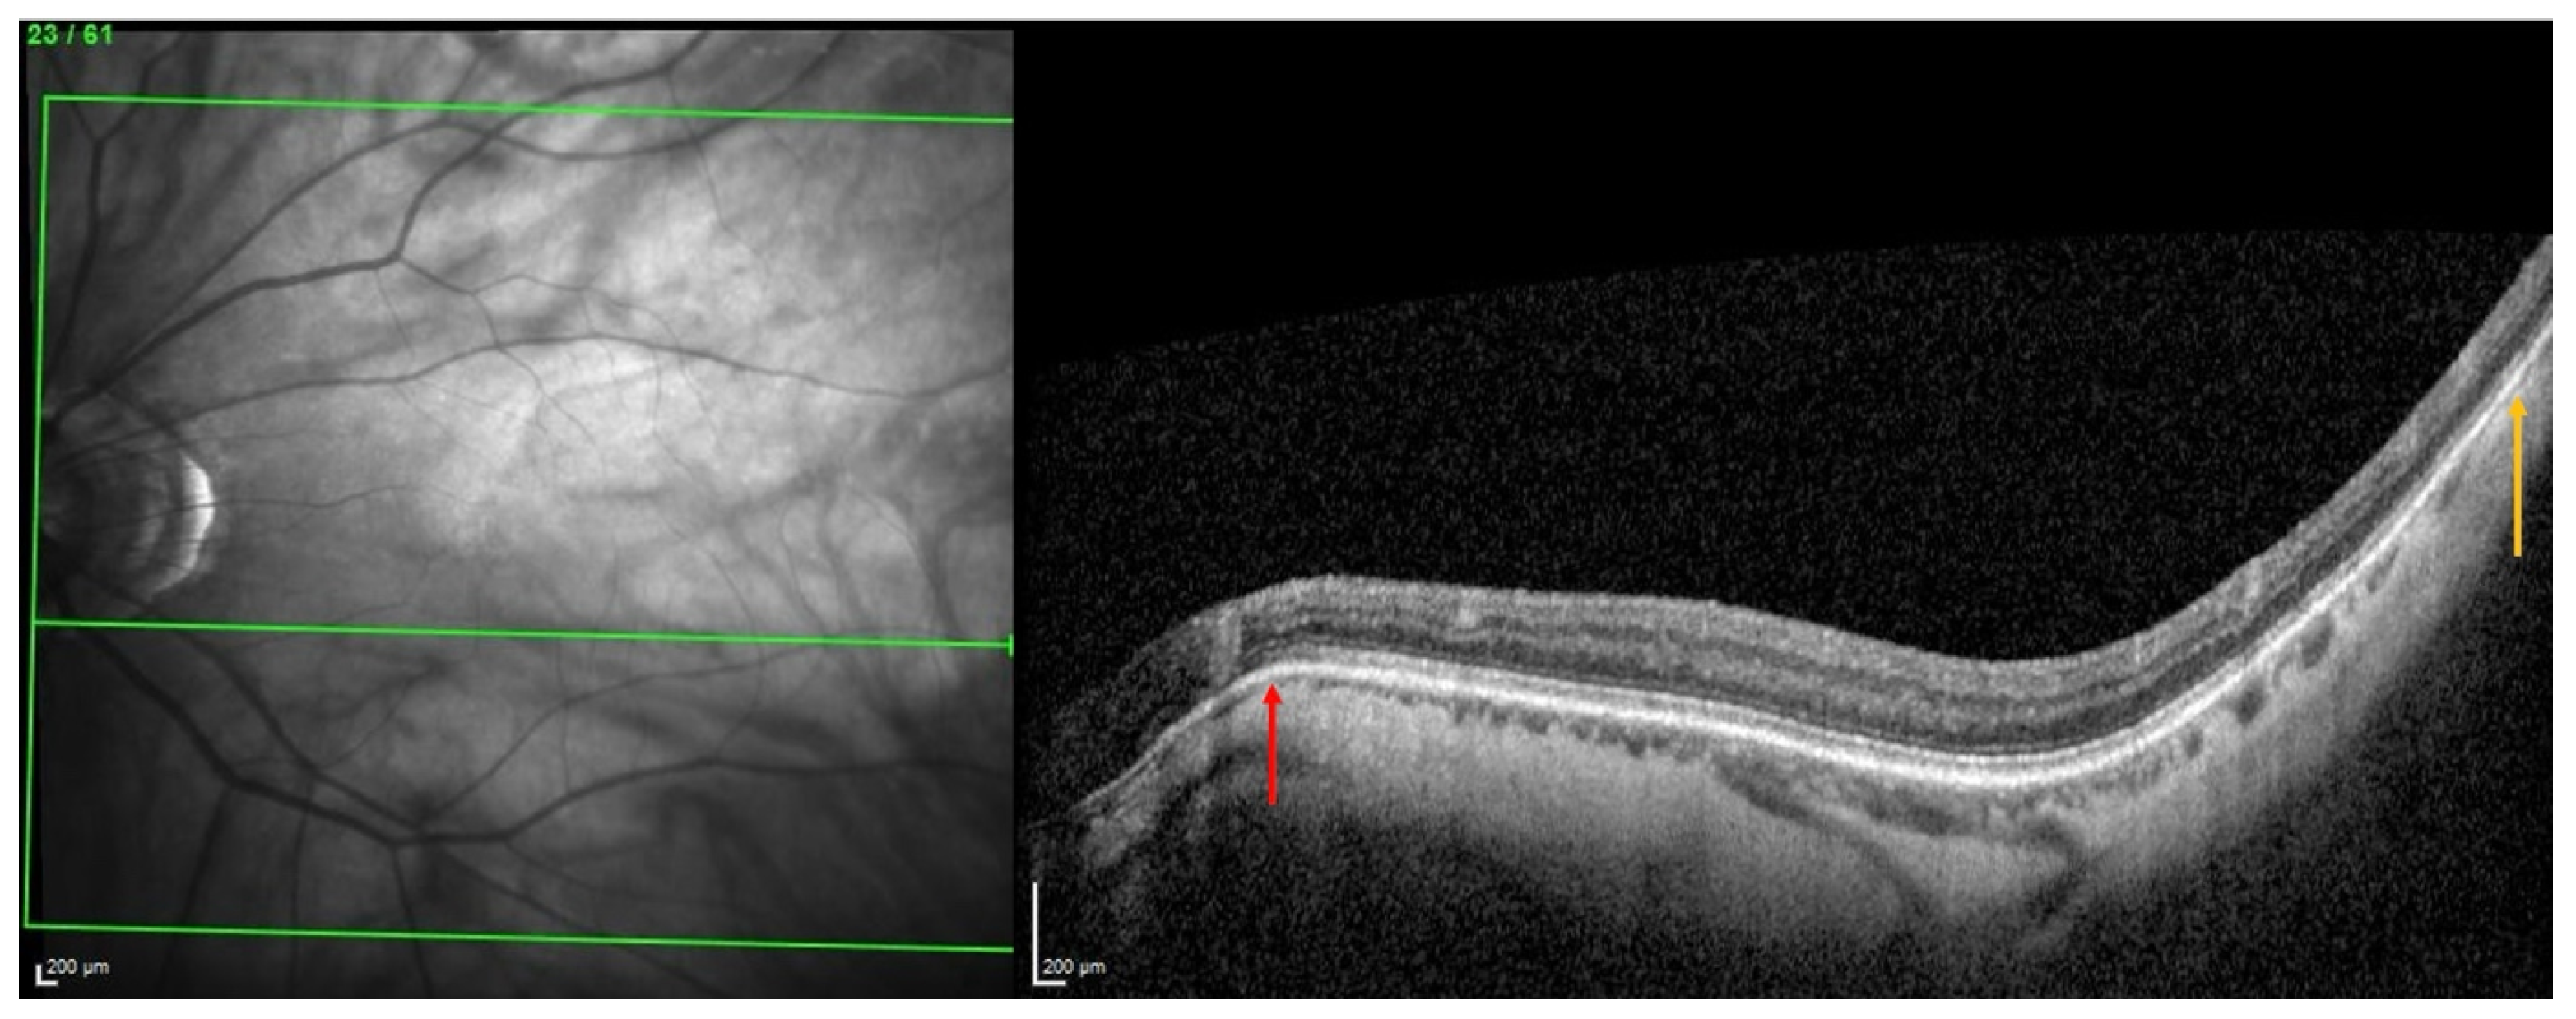

For each of the three locations, choroidal thinning was considered present when the thinning was noted in at least three adjacent sections (Figure 2A–C), emphasized in (Figure 2D–F).

Figure 2.

The diagnosis of a choroidal thinning within the band centered by the fovea–Bruch’s membrane opening axis. This diagnosis was retained if a thinning was noted in at least three consecutive sections (dashed red arrows) in (A–C). Section numbers are highlighted by the yellow arrows in (A–C). The green lines in (A–C) locate the corresponding OCT slices. The yellow rectangles in (A–C) are presented in (D–F), respectively.

The representative OCT scans of FT-distance in different locations and the corresponding AL and FT-distance values are presented in Figure 5A–C.

Figure 5.

(A) Thinning above the FoBMO axis. Thickness of the thinning: 170 µm. Fovea-thinning distance: 2711 µm. Axial length: 22.04 mm. (B) Thinning along the FoBMO axis; 5B1. Marks of the fovea (red arrow) and the thinning (black arrow) in the IR image; 5B2. Fovea-thinning distance measured between these marks. Thickness of the thinning: 174 µm. Fovea-thinning distance: 3987 µm. Axial length: 23.94 mm. (C) Thinning below the FoBMO axis. Thickness of the thinning: 18 µm. Fovea-thinning distance: 4236 µm. Axial length: 29.86 mm. The yellow box is presented in (C). The red curve underlines the posterior choroidal wall. The green horizontal lines in the infrared images locate the OCT sections. (A–C) The vertical green lines in the OCT sections locate the thinnings which appears as a discontinuity within the horizontal green line of each corresponding infrared image. Abbreviation: FoBMO = Fovea-Bruch’s membrane Opening.

From this, it was suggested that the underlying pathogenesis of some forms of PS involves inward scleral deformation by compression forces and its outward deformation by traction forces [4,5,13] applied by ON sheaths [4,5] or oblique muscles [13]. The repetition of these deformations over time would lead to a remodeling and fixation of the tissues in the deformed configuration [4,5,13] (Figure 7).

Figure 7.

Illustration of two choroidal thinnings related to scleral inward deformations. The choroidal thinning at the peripapillary zone (red arrow) would result from squeezing by the optic nerve sheaths, while the other thinning, temporal to the macular position (yellow arrow), would be related to the action of the inferior oblique muscle.